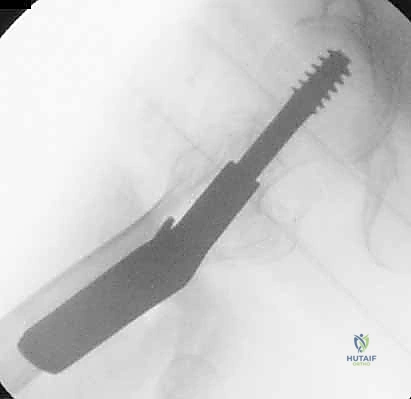

5. الحفر وتثبيت الغرسة (Reaming and Implantation)

يتم استخدام أداة حفر مجوفة تمر فوق السلك الدليلي لتوسيع مسار في العظم. بعد ذلك، يتم إدخال المسمار الرئيسي القوي (سواء المسمار المنزلق أو المسمار النخاعي).

4. إدخال السلك الدليلي (Guide Wire)

يتم إدخال سلك معدني رفيع جداً عبر العظم باتجاه رأس الفخذ تحت توجيه الأشعة المستمر. هذا السلك يعمل كمسار دقيق سيتبعه المسمار النهائي. يجب أن يكون السلك في الموضع الهندسي المثالي لتجنب اختراق مفصل الورك.

مجموعة من الصور الإضافية التي توضح مراحل دقيقة من العمل الجراحي المعقد الذي يجريه الأستاذ الدكتور محمد هطيف لضمان أعلى درجات الدقة الميكانيكية الحيوية: